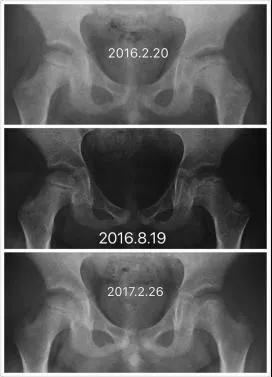

Perthes病即儿童股骨头特发性缺血性骨软骨病,于1910年被Legg、Calve、和Perthes三位学者总结报道,因此也称为Legg-Calve-Perthes病,简称LCPD。发病早期,患儿往往出现跛行和患侧大腿中下段的疼痛不适、有时甚至是健侧膝盖周围疼痛,休息几天就可以缓解。但由于儿童天性活泼好动,上述症状常常容易复发。因此好多孩子常常被家长乃至初诊医生忽视、只是简单认为是“滑膜炎”、“缺钙”或者所谓“生长痛”,没有早期发现并且及时确诊、科学施治,而遗留了头臼曲率适应不佳、髋臼覆盖不良、股骨近端形态异常等等生长发育畸形(图1),导致髋关节出现软骨磨损继而早发骨性关节炎,从而严重影响日常生活和工作。而如果能够早发现早治疗,LCPD完全可以获得优良结果乃至正常髋关节状态(图2)!

图1 LCPD影像学表现,股骨头变形,髋关节覆盖差